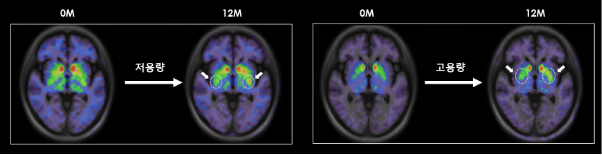

TED-A9 이식 1년 후 뇌영상 이미지 ([18F]FP-CIT PET)에서 투여 전 베이스라인 대비 도파민 수송체(DAT)의발현이 증가되었음을 확인하였으며(그림 참조), 해당 뇌영상결과 저용량군에 비해 고용량군에서 도파민 세포 생착 신호가 더 높게 측정되었다. 이러한 결과는 이식된 TED-A9이 뇌 속에서 생존하여 도파민 신경세포로 성숙되고 주변부와 시냅스를 형성하고 있다는 것을 시사하며, 사멸된 도파민 신경세포를 대체하는 파킨슨병의 근본적인 치료 메커니즘에 대한 증거라고 볼 수 있다.